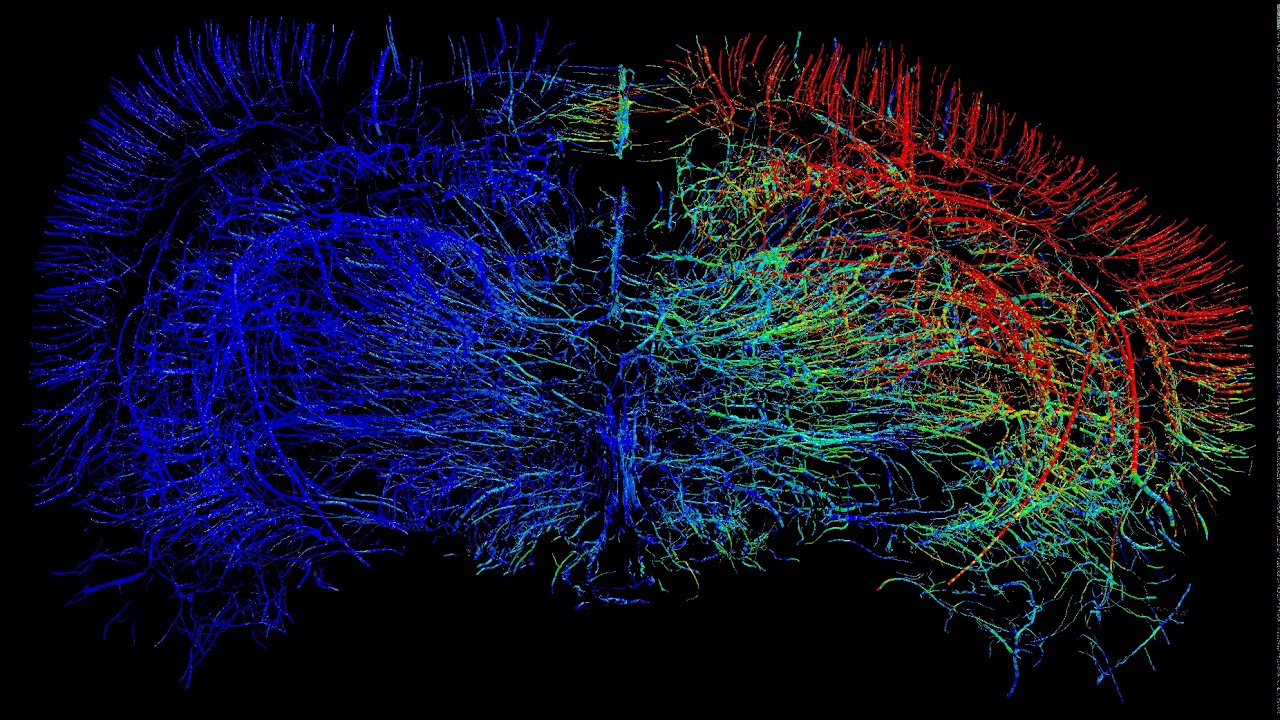

Vascular Injury Rat Brain Impact Simulation